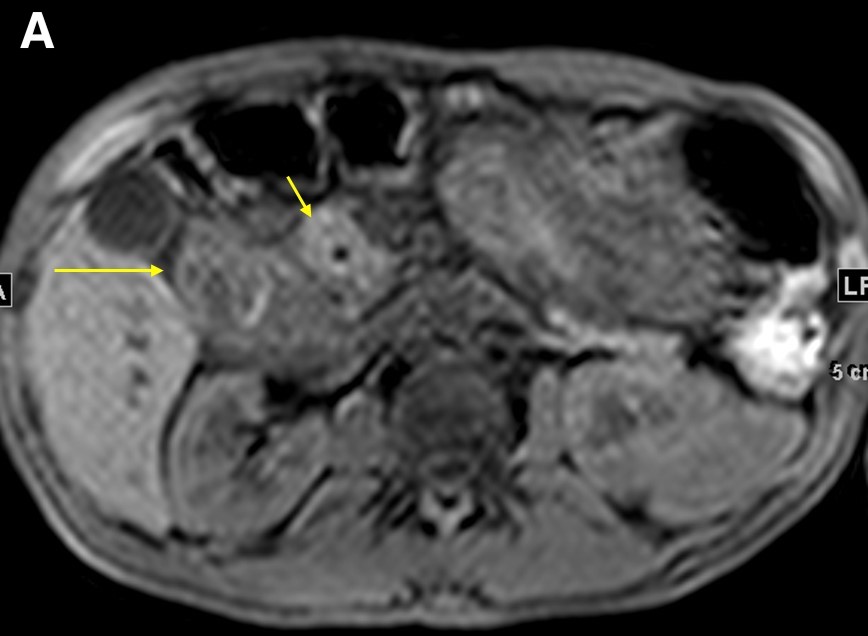

On magnetic resonance imaging (MRI) scans, groove pancreatitis often shows a T1 hypointense “sheet like” mass in the groove space.6 Depending on timing, T2 can demonstrate hypointensity, isointensity, or hyperintensity in this region.1 The initial phase of disease shows T2 hyperintensity, with progression into isointensity or hypointensity caused by fibrosis as the disease course continues.1 Cysts or cystic masses can be seen in the duodenal wall or groove space in T2-weighted imaging, as we saw in our patient (Figure 3).1 Magnetic resonance cholangiopancreatography can be helpful, as it can also demonstrate nonspecific signs such as common bile duct/pancreatic duct dilation.1 Gadolinium-enhanced images show delayed enhancement caused by fibrosis, as we saw in our patient (Figure 4). In one study, approximately 93% of patients showed patchy, late, post-gadolinium enhancement of the pancreas.7 In both the pure and segmental forms of groove pancreatitis, authors of one study found medial wall of the duodenum involvement with mural cysts on T2 weighted imaging.8 In cases of segmental groove pancreatitis, the common bile duct shows gradual tapering, while in cases of malignancy, the duct shows abrupt cutoff, which we saw in our patient (Figure 5).6

Figure 4. Precontrasted fat saturated T1WI sequence demonstrated the pancreatic head (a, short arrow) and duodenal wall thickening (a, long arrow). The 5-minute post-contrast T1WI sequence demonstrated an intramural cyst in the thickened wall, with delayed enhancement in the groove region and no discrete mass (b, arrow).